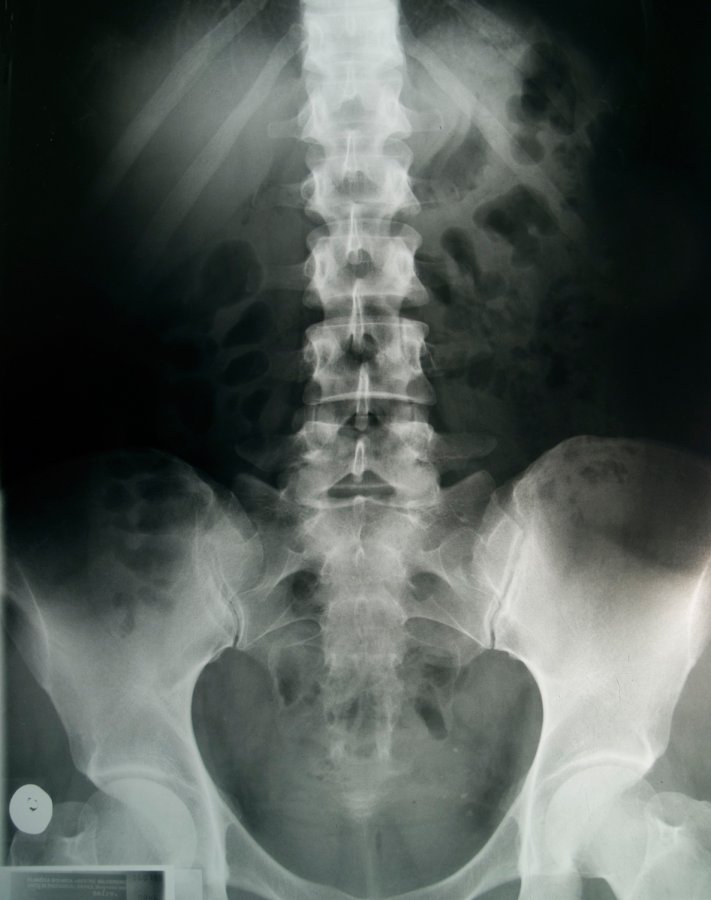

O Raio X é um exame que extrai imagens de qualquer parte do corpo por meio do uso de raios-x.

É utilizado com frequência como método inicial na avaliação de várias patologias, pois permite a avaliação anatômica e funcional dos sistemas e aparelhos do organismo humano.​

A radiação sai do equipamento de raio x, atravessa o corpo do paciente e penetra o filme radiográfico formando as imagens, que depois serão analisadas pelo médico.

​​Entre outras coisas, a Radiologia Geral ou de Raio X identifica:

• Fraturas ósseas;

• Tumores ósseos;

• Distúrbios de crescimento e postura;

• Possibilita o estudo das articulações/ artrose;